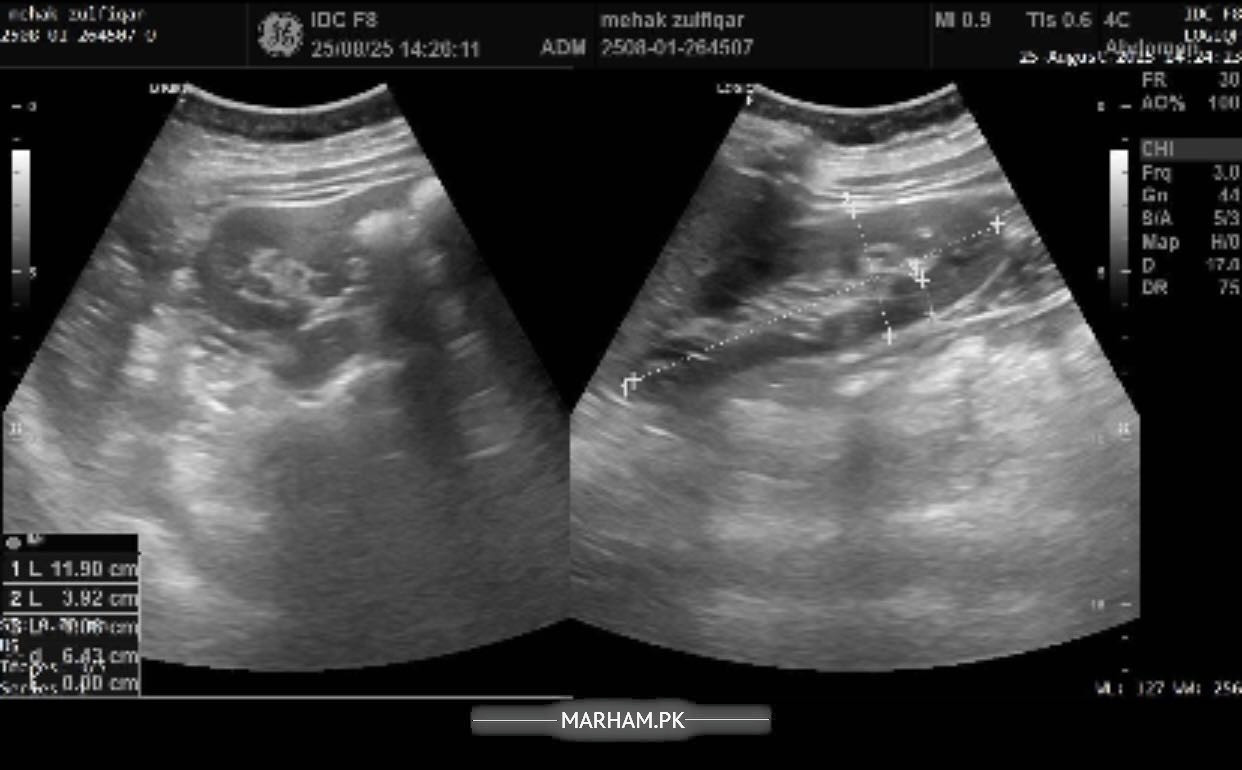

Pain in the right side of abdomen under the ribs followed by backache in the same area. In addition to these symptoms having difficulty concentrating, having confusion, difficulty speaking facial muscles hurt, sleepiness all the time, fluctuations in bp and feel nauseous with sometimes developed fever or shivering. Please help me with this. Will be highly thankful. Attached my reports too.

Sr this is the most recent ultrasound report. But radiology isn’t matching my blood reports. I am worried about that. Pls help.

report of ultrasound

you’re demonstrating features of UTI, blood in urine can be due to many things, would like to explore this in detail and get to do few more tests. I’m available for consultation

Okay I think you need proper consultation, and a proper ultrasound from a consultant. I’m available or if you want to see anybody of your liking you should. in the meantime i need you to make a record of your bp for a week, 2 readings in the morning and 2 readings at night then tell me